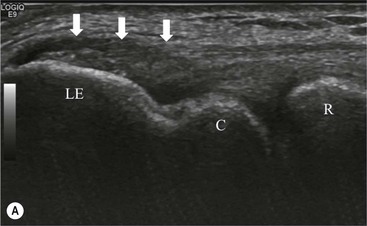

The affected tendon is thickened and hyporeflective on US, with neovascularisation on Doppler imaging (Fig. 46-16). High SI is demonstrated on fluid-sensitive MRI sequences (Fig. 46-17). Tendon tears are demonstrated as focal areas of deficiency.13 In chronic cases, new bone formation may be seen on radiographs at the tendon enthesis. Calcific tendinopathy is much less common than in the rotator cuff of the shoulder.

The distal biceps tendon inserts on the tuberosity of the proximal radius. It does not have a tendon sheath, but surrounding connective tissue is known as a paratenon. It is surrounded near the insertion by the bicipitoradial bursa. Distal biceps tears are often clinically unrecognised, but may be amenable to surgery if diagnosed early. In the early stages the tendon is thickened and there may be an effusion in the bicipitoradial bursa (Fig. 46-18). In complete rupture the tendon retracts proximally. MRI and US may be used to confirm the diagnosis and locate the tendon end (Figs. 46-19 and 46-20).